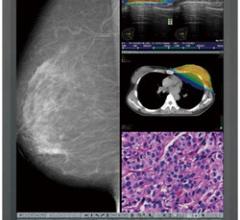

iCAD Inc. announced that researchers presented updated data on the use of intraoperative radiation therapy (IORT) with the Xoft Axxent Electronic Brachytherapy (eBx) System during the San Antonio Breast Cancer Symposium (SABCS), Dec. 6-10 in San Antonio, Texas. The data include results from a subset of patients who received IORT with the Xoft System as a boost prior to administration of whole breast radiation therapy (WBRT) in patients with early-stage breast cancer.

Despite decades of progress in breast imaging, one challenge continues to test even the most skilled radiologists ...